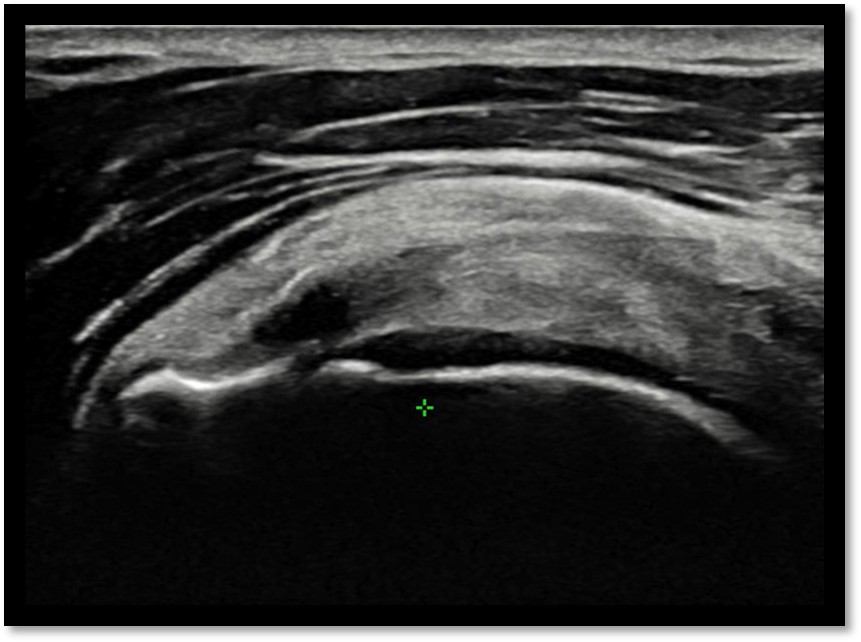

MRI와 초음파를 다시 검토했습니다.

회전근개 극상건의 관절면측(articular-side) 부분파열.

Step 2: 초음파 유도 하 가이드 삽입

초음파로 파열 부위를 실시간 확인하면서 특수 가이드를 삽입합니다.

Step 6: 확인 및 마무리

초음파로 봉합 상태를 확인하고 마무리합니다.

봉합 부위 안정성 확인